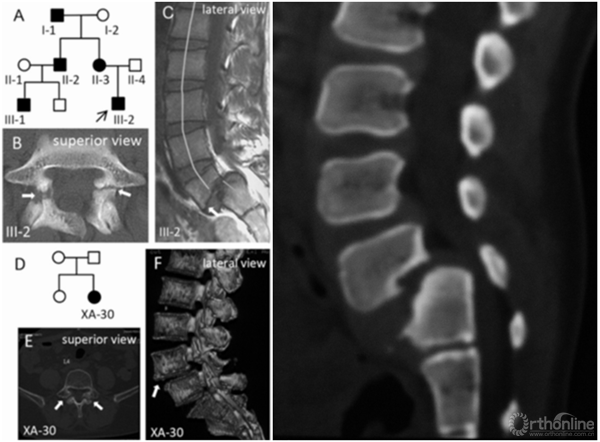

1. 骶骨形态重度不良

对重度骶骨发育不良者,先天遗传是主要原因。2015年,罗卓荆团队通过两个家系[6],鉴定了2个新型错义突变,功能研究显示软骨发育过程中,磷酸化摄入障碍是其发病主要的分子机制。遗传因素造成的骶骨穹窿形态不良,通常较为严重,并会造成L5椎体梯形变,导致滑脱进展,并使得外科治疗此类畸形较为困难。